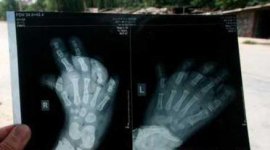

یک دختر بچه 3 ساله چینی از یک بیماری رنج می برد که باعث شده است پاهای وی بزرگتر از حد معمول خود باشند. یو یو دختر بچه 3 ساله چینی دارای بیماری عجیبی است که این بیماری باعث می شود پاهای این دختر بچه با سرعت بسیار بالایی رشد کنند.

پاهای یو یو دائما در حال متورم و سنگین شدن هستند که راه رفتن را برای او بسیار دشوار کرده است.

خانواده این دختر بسیار فقیر هستند و از مخارج معالجه دخترشان بر نمی آیند ولی پدر بزرگ یو یو در حال جمع آوری و به دست آوردن پولی است که بتواند نوه خود را درمان کند.